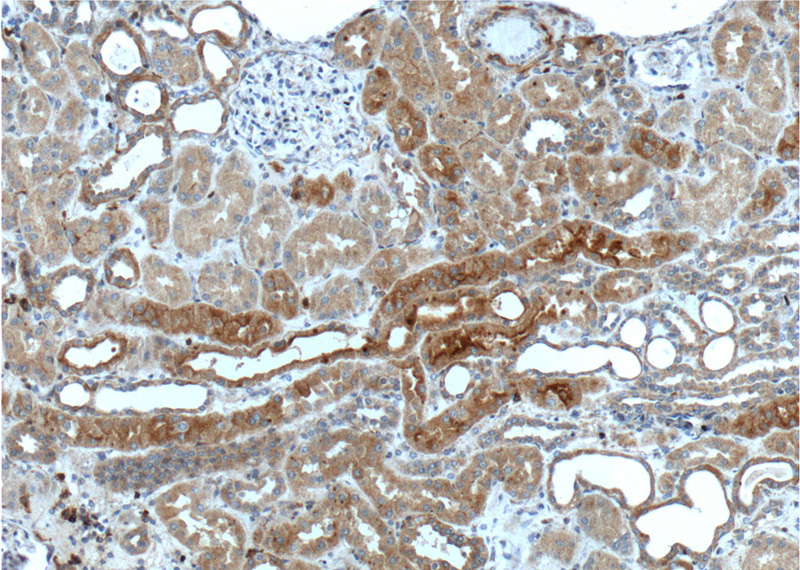

Immunohistochemistry of paraffin-embedded human kidney tissue slide using Catalog No:113308(NOTCH1 Antibody) at dilution of 1:200 (under 10x lens).